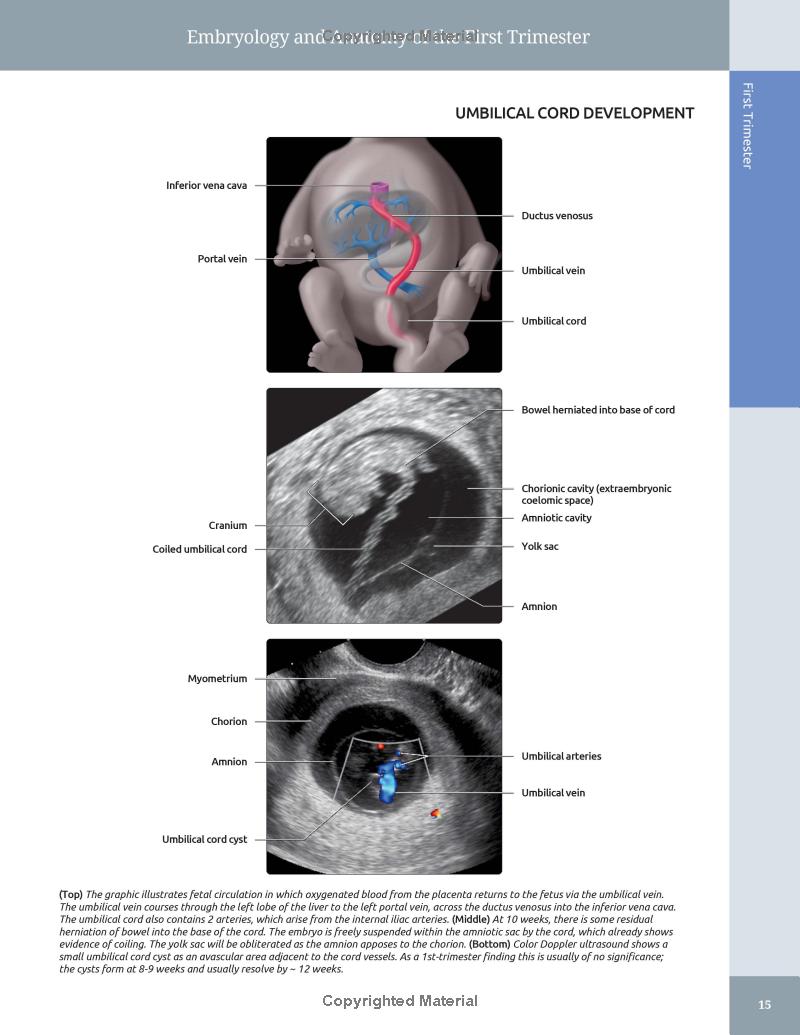

- Features expanded embryology chapters delineating normal developmental anatomy

- Richly colored graphics and fully annotated images highlight the most important diagnostic possibilities